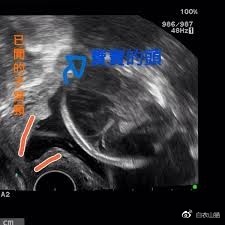

B超诊断子宫颈闭锁不全

现在,可以用B超来诊断子宫颈的早期扩张,利用B超检查子宫颈“漏斗”状变化与子宫颈长度,来诊断子宫颈闭锁不全。